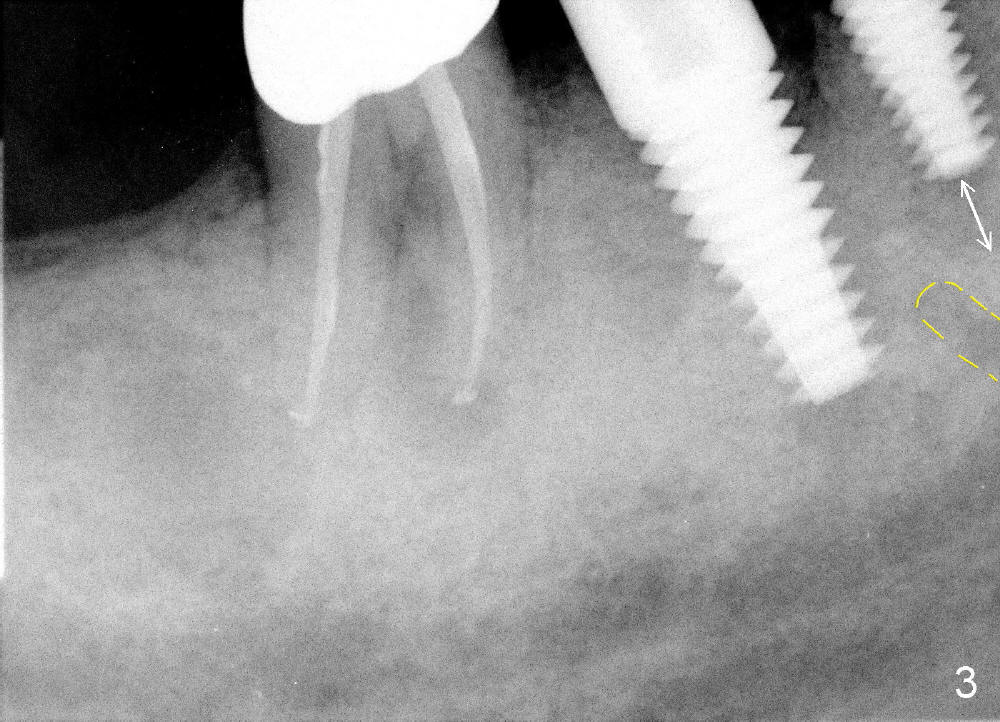

One month after implant placement at the sites of #29,30, the former is found loose (Fig.1,2). It is placed higher than #30. Three weeks later, PA is retaken to confirm that there is space apical to the implant at #29 (Fig.3 double arrows) and that there is distance from the mental loop (yellow dashed line). After infiltration anesthesia, the implant is torqued down initially (compare Fig.4,5) and more (Fig.6,7). To prevent re-loosening, the two implants are splinted (Fig.8).

In 3 months, the gingiva appears to have grown up to cover more of the most coronal portion of the implants (Fig.9). Since the tooth #31 becomes symptomatic probably due to overloading (Fig.10), these 2 implants are prepared for restoration ahead of time.